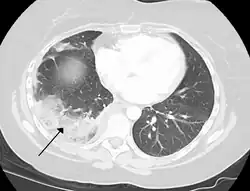

Blood-supply changes

Tissue death of the lung due to a pulmonary embolism

A pulmonary embolism is a blood clot that becomes lodged in the pulmonary arteries. The majority of emboli arise because of deep vein thrombosis in the legs. Pulmonary emboli may be investigated using a ventilation/perfusion scan, a CT scan of the arteries of the lung, or blood tests such as the D-dimer.[74] Pulmonary hypertension describes an increased pressure at the beginning of the pulmonary artery that has a large number of differing causes.[74] Other rarer conditions may also affect the blood supply of the lung, such as granulomatosis with polyangiitis, which causes inflammation of the small blood vessels of the lungs and kidneys.[74]